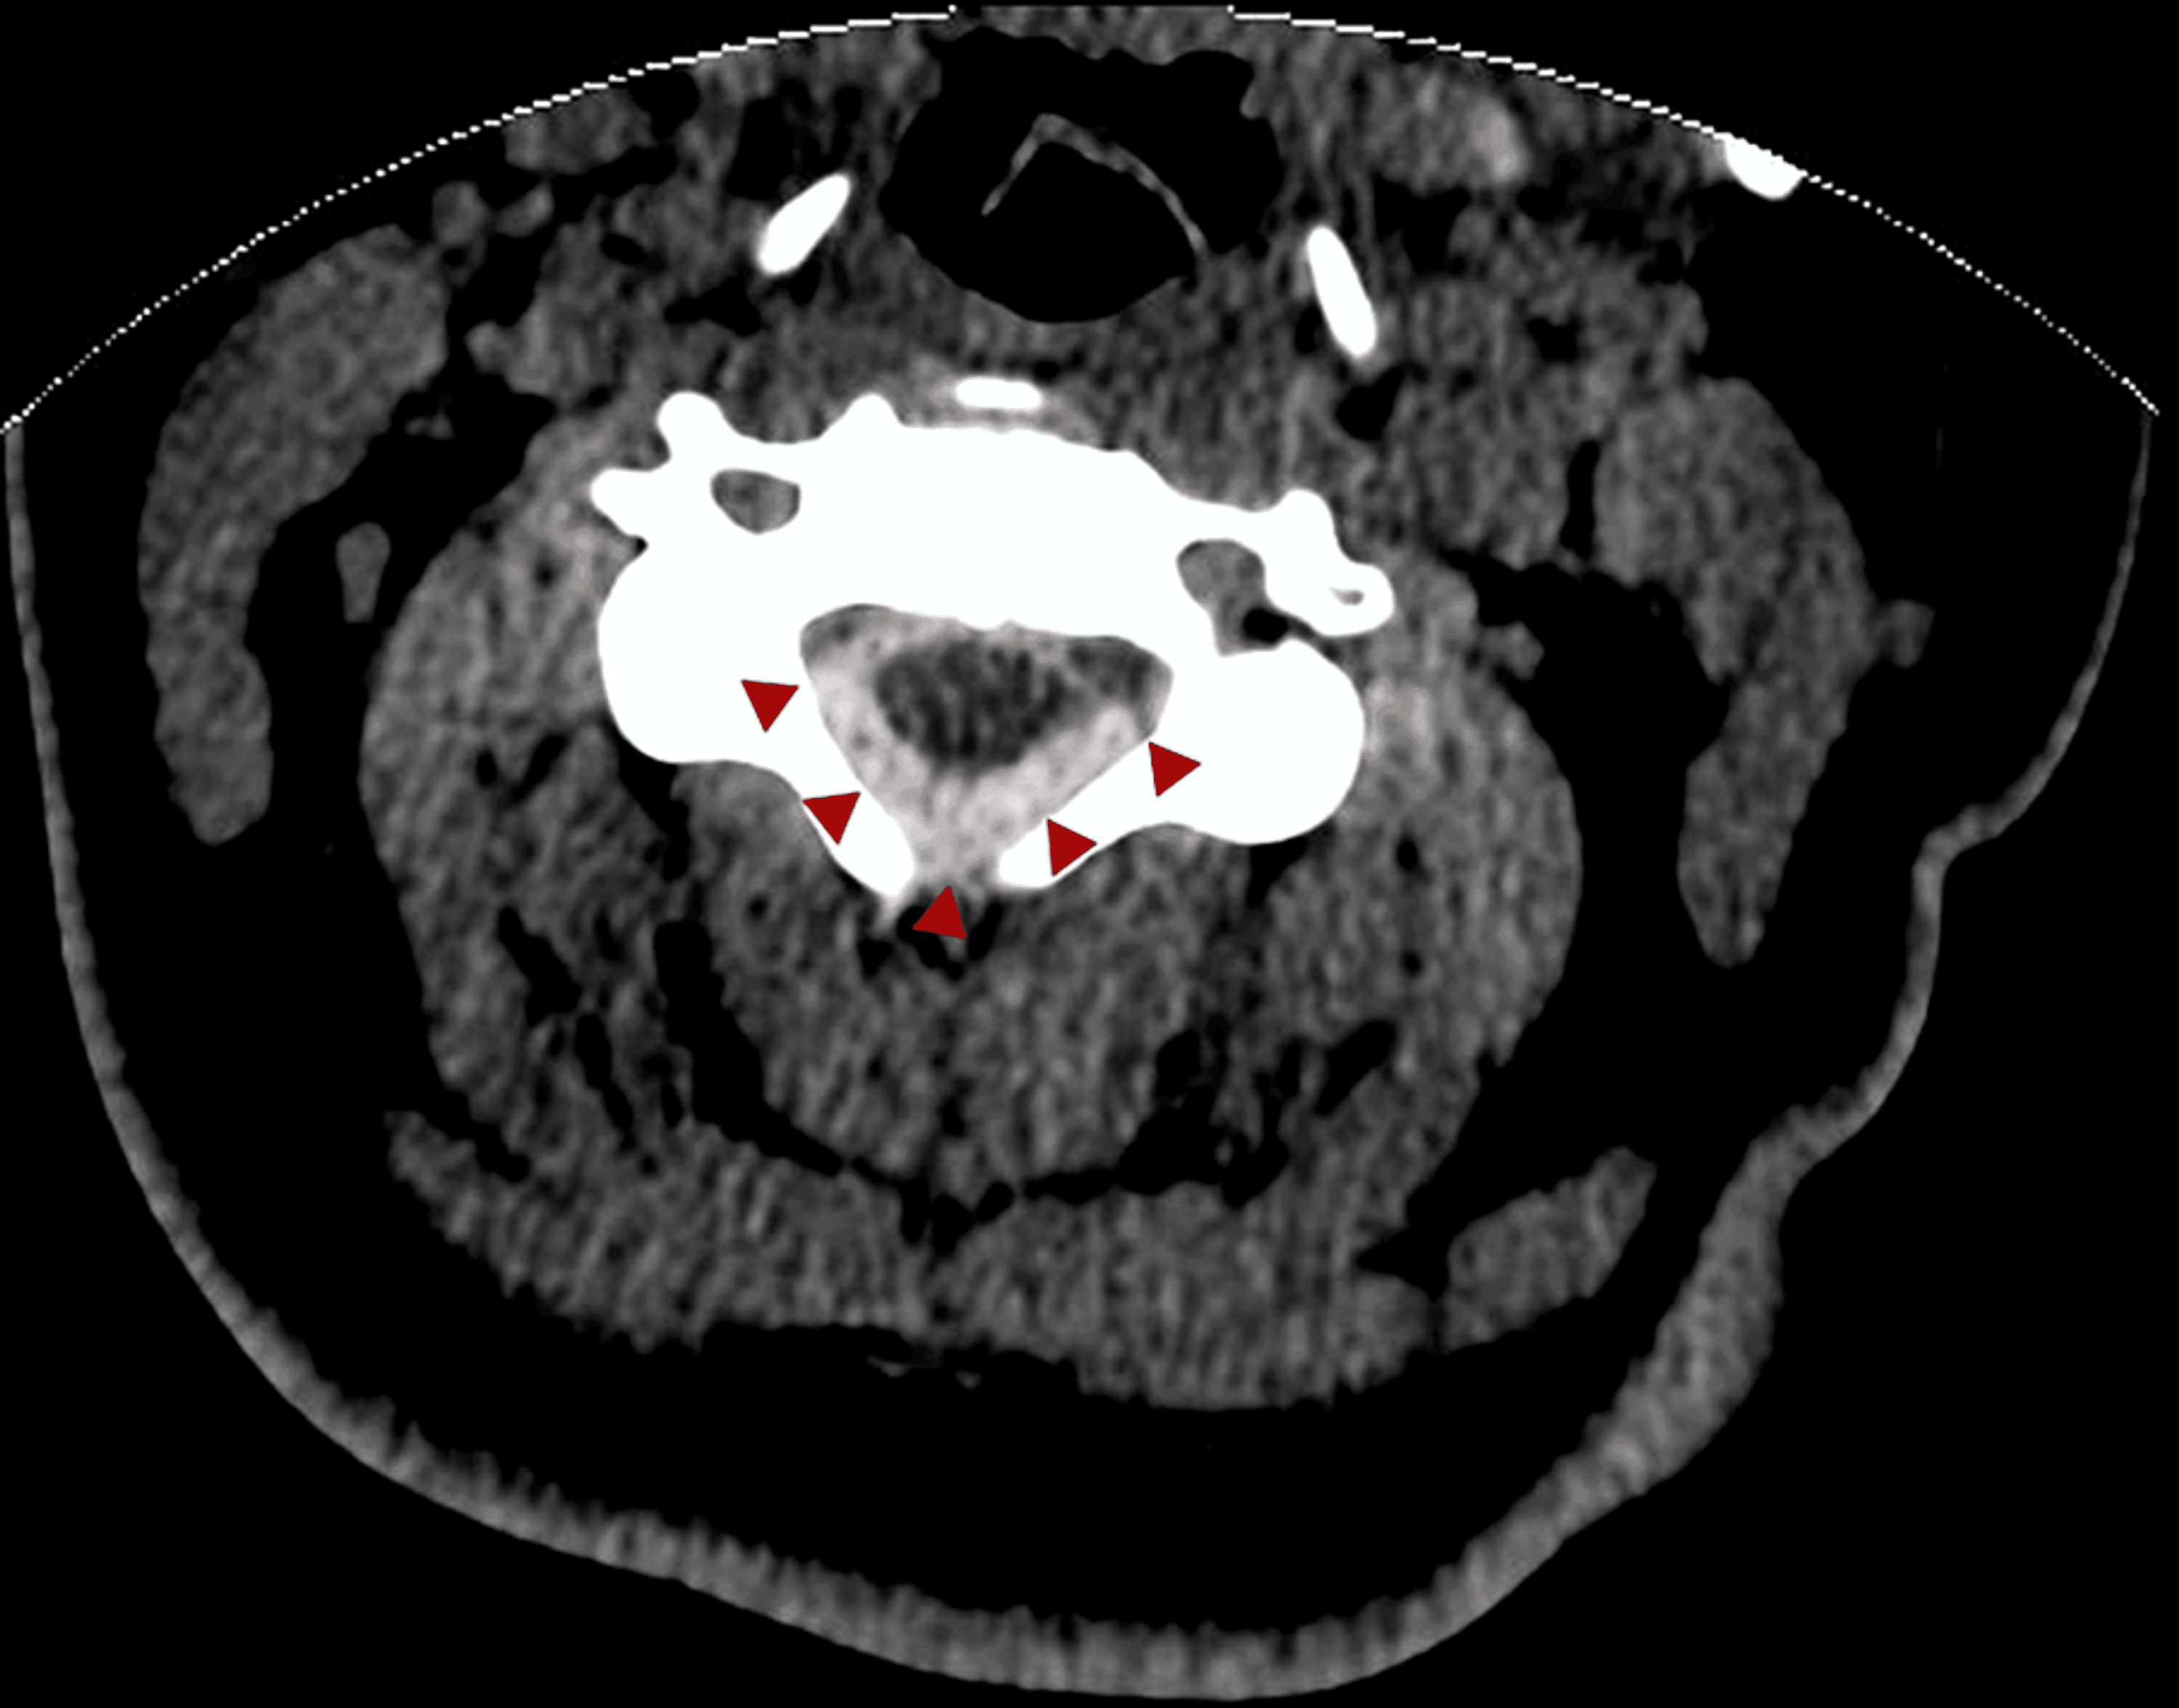

First CT appearance (A) hemorrhage in the thoracic cord; (B & C) after Cord Hemorrhage It most commonly is caused by trauma, vascular malformations, or bleeding diatheses and can be. Spinal cord hemorrhages are rare conditions that can be classified based on the primary location of bleeding into intramedullary (hematomyelia), subarachnoid hemorrhage (sah),. Spinal cord hemorrhages are rare conditions that can be classified based on the primary location of bleeding into intramedullary (hematomyelia),. Spinal cord. Cord Hemorrhage.